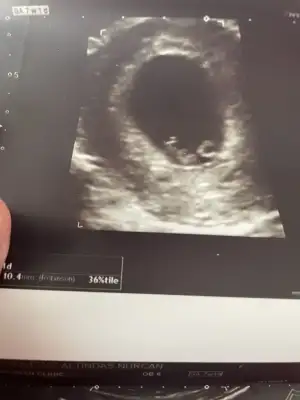

Karından ultrason muydu cnm?Kızlar merhaba 10 haftalık hamileyim. Keseye göre cinsiyet tahmini yapabilir misiniz? Yuvarlak kese kız, uzun muz gibi olan kese erkek olur diyorlar. Benimki nasıl sizce? Çok çok heyecanlıyım

İlk halini de ekledim :)